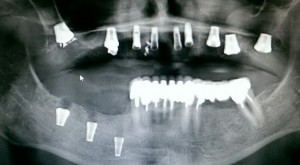

Цель имплантологического лечения — не воткнуть импланты так, чтобы они прижились, а создание надёжной и долговечной опоры под планируемую ортопедическую конструкцию.

В настоящий момент производители выпускают линейки имплантов, предназначенных для установки в лунку только что удаленного зуба. Они отличаются крупной агрессивной резьбой, назначение которой – обеспечить качественную стабилизацию импланта в условиях лунки только что удаленного зуба.

А всё дело в том, что некоторые пациенты (и некоторые доктора) рассматривают импланты, установленные в костной ткани, именно как гвозди забитые в деревянную доску. Отсюда возникает ошибочное умозаключение — чем плотнее кость (дерево), тем лучше держится имплантат (гвоздь).